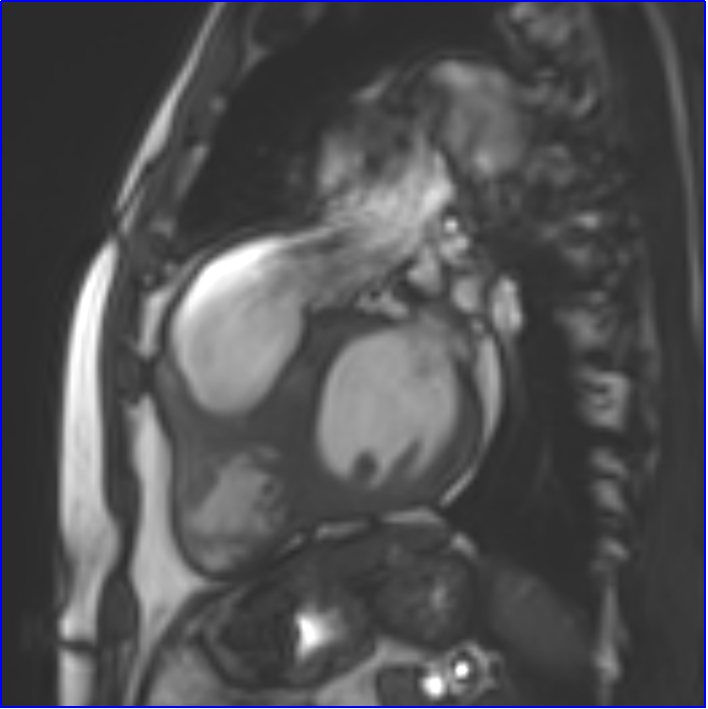

术前心脏磁共振成像评估

心脏法洛四联症术后改变。右心房、右心室增大:舒张末期左室短径 4.9cm,长径 9.3cm;右室短径 5.7cm,长径 10.0cm;心室收缩末期,三腔心层面左房前后径2.7cm,左室流出道形态欠规则,宽度1.5cm;四腔心层面左房大小4.4cm×4.4cm,右房大小 5.7cm×5.0cm。舒张末期室间隔厚约8-9mm,左室侧壁厚约6-7mm;右室游离壁心肌局部略厚,舒张末期最厚约4mm。T2W黑血序列示心肌信号未见明显异常。心包未见明显积液信号。升主动脉直径约3.9cm;主肺动脉增宽,直径约3.7cm。下腔静脉及肝静脉未见明显增宽。右室流出道形态不规则,可见成角,肺动脉瓣水平较窄,肺动脉瓣反流明显,三尖瓣、主动脉瓣少量反流信号。动态电影序列示右室收缩运动减弱;勾画心腔轮廓测量左心功能:左室射血分数(LVEF):60.1%,左室舒张末容积(LVEDV):127.2ml,左室收缩末容积指数:31.3 ml/m²,左室舒张末容积指数:78.4 ml/m²;右心功能:右室射血分数(RVEF):43.5%,右室舒张末容积(RVEDV):268.6 ml,右室收缩末容积指数:93.5ml/m²,右室舒张末容积指数:165.6 ml/m²。RVEDV/LVEDV 2.11。肺动脉瓣反流分数55.2%。

心脏磁共振成像右室流出道电影图像示法洛四联症术后,右心室流出道形态欠规则,肺动脉瓣水平反流信号